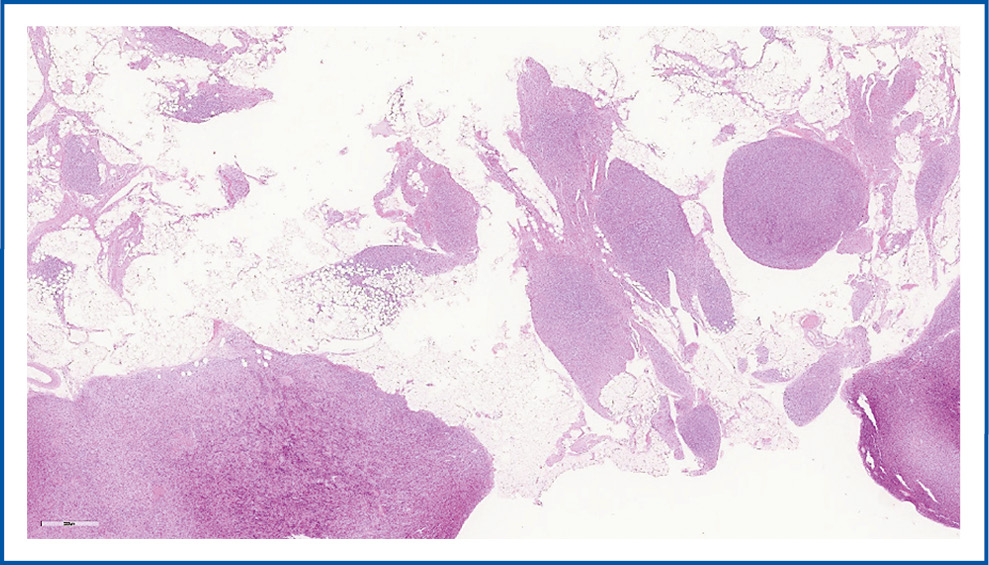

Гистологическое исследование: в ТМ определяются множественные четкие беловатые узлы, плотноэластической консистенции, на разрезе слоистые. Микроскопически хорошо очерченные множественные узлы с четкими границами, представленные переплетающимися пучками мономорфных удлиненных веретенообразных клеток с обильной эозинофильной цитоплазмой, ядрами овальной формы, незаметными ядрышками. Некроз, фигуры митозов и сосудистая инвазия в опухоли не определяются. Установлен диагноз многоузловой ЛММ (рис. 1).

Рис. 1. ЛММ. Окраска гематоксилин-эозином, ×20.

Fig. 1. Uterine leiomyoma (ULM). Hematoxylin and eosin staining, ×20.